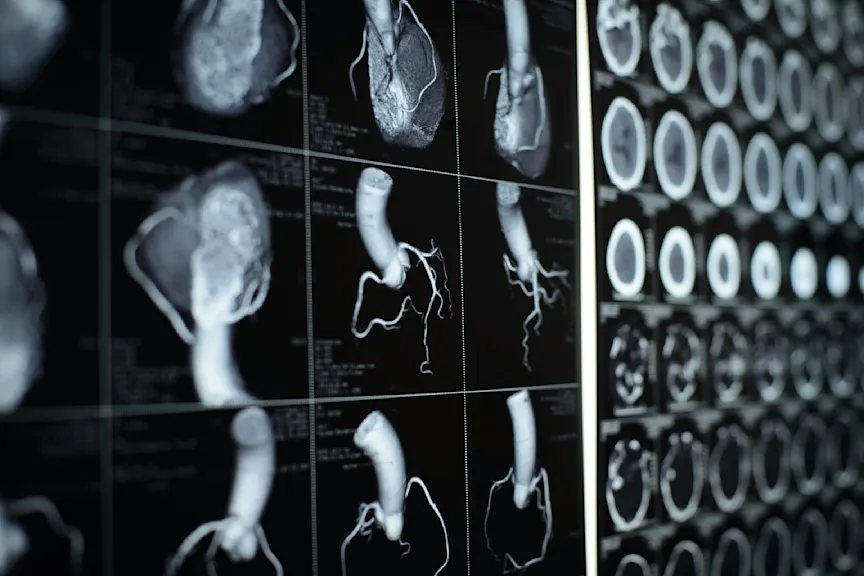

CT扫描

计算机断层扫描,也称为多探测器CT(或MDCT),使用多个快速x射线创建详细的,你跳动的心脏的横断面图像。这些图像可以精确定位阻塞点和钙沉积,这些可能会阻止阀门完全打开或关闭。这种检查通常作为一种微创的替代方法在手术干预前进行,以帮助指导外科医生。多层螺旋ct的过程很像核磁共振成像;你将躺下,然后被引导进入一根管子,在扫描过程中进行5到10分钟。电极可能被放置在你的胸部,有时通过静脉注射造影剂在你的手臂静脉,被使用。